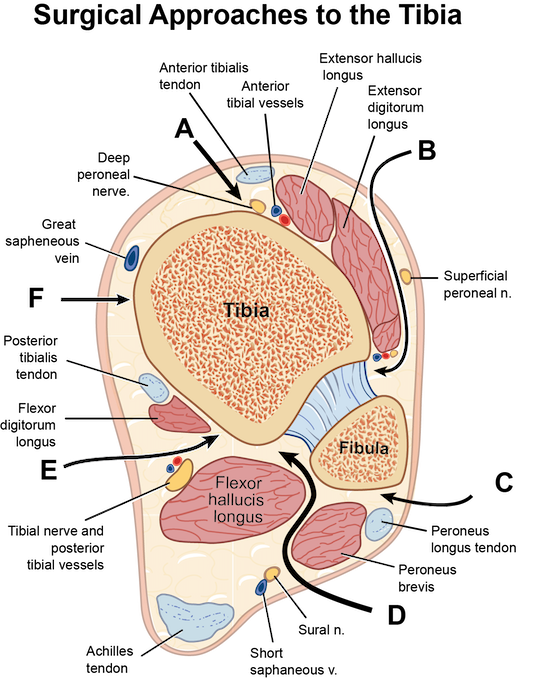

Surgical illustrations visually depict operative techniques, surgical anatomy, and complex procedures. They are created with high anatomical accuracy and serve as a visual bridge between complex surgical knowledge and learners, clinicians, or patients.